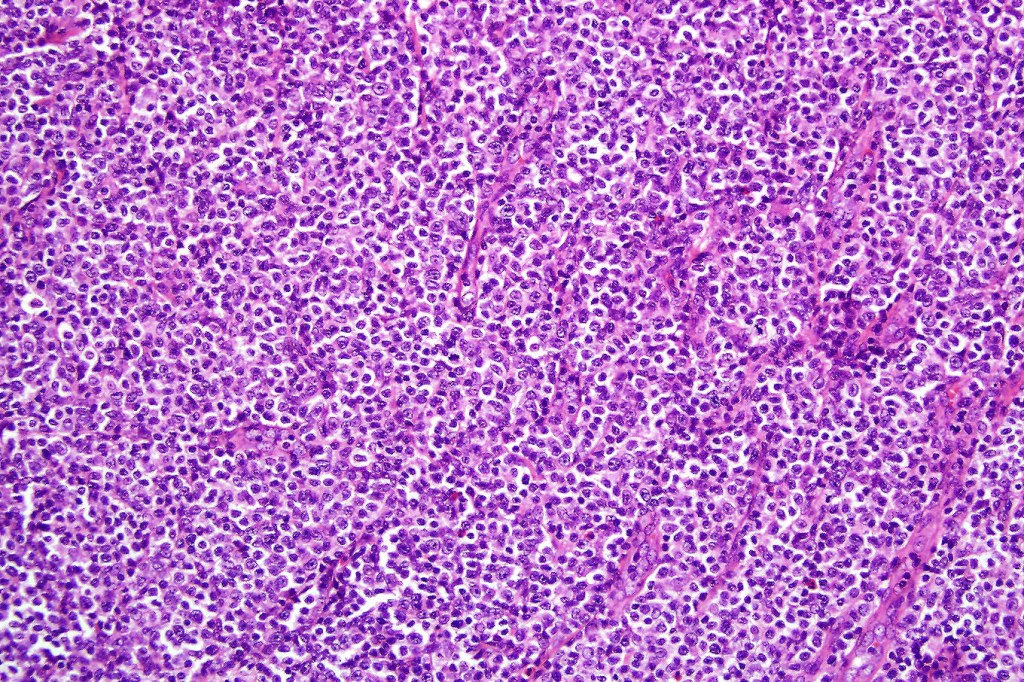

Histological features

The histological hallmark of mycosis fungoides is the presence of large atypical lymphocytes with a convoluted/cerebriform nuclear border (Sézary cells). These may be found at the epidermal-dermal jnuction and as collections within the epidermis (Pautrier microabscess). These are most easily found in plaque stage disease. The epidermal component can be subtle in patch stage disease and is often lost in tumor stage dsease. The classification into patch, plaque & tumor stage disease is less helpful histologically as the features merge from one to the other. It is all a matter of degree.

Tumor Stage Disease

•Epidermotropism is often minimal or absent

•Dense, broad diffuse or nodular, dermal infiltrate often extending into the subcutaneous fat

•Abundant Sézary cells. Frequently accompanied by very pleomorphic forms

•Mitoses often abundant, frequently abnormal

•CD30 expression correlates with transformation (cells X4 size of small lymphocytes comprising 25% or more of the infiltrate or the presence of a distinct large nodule)